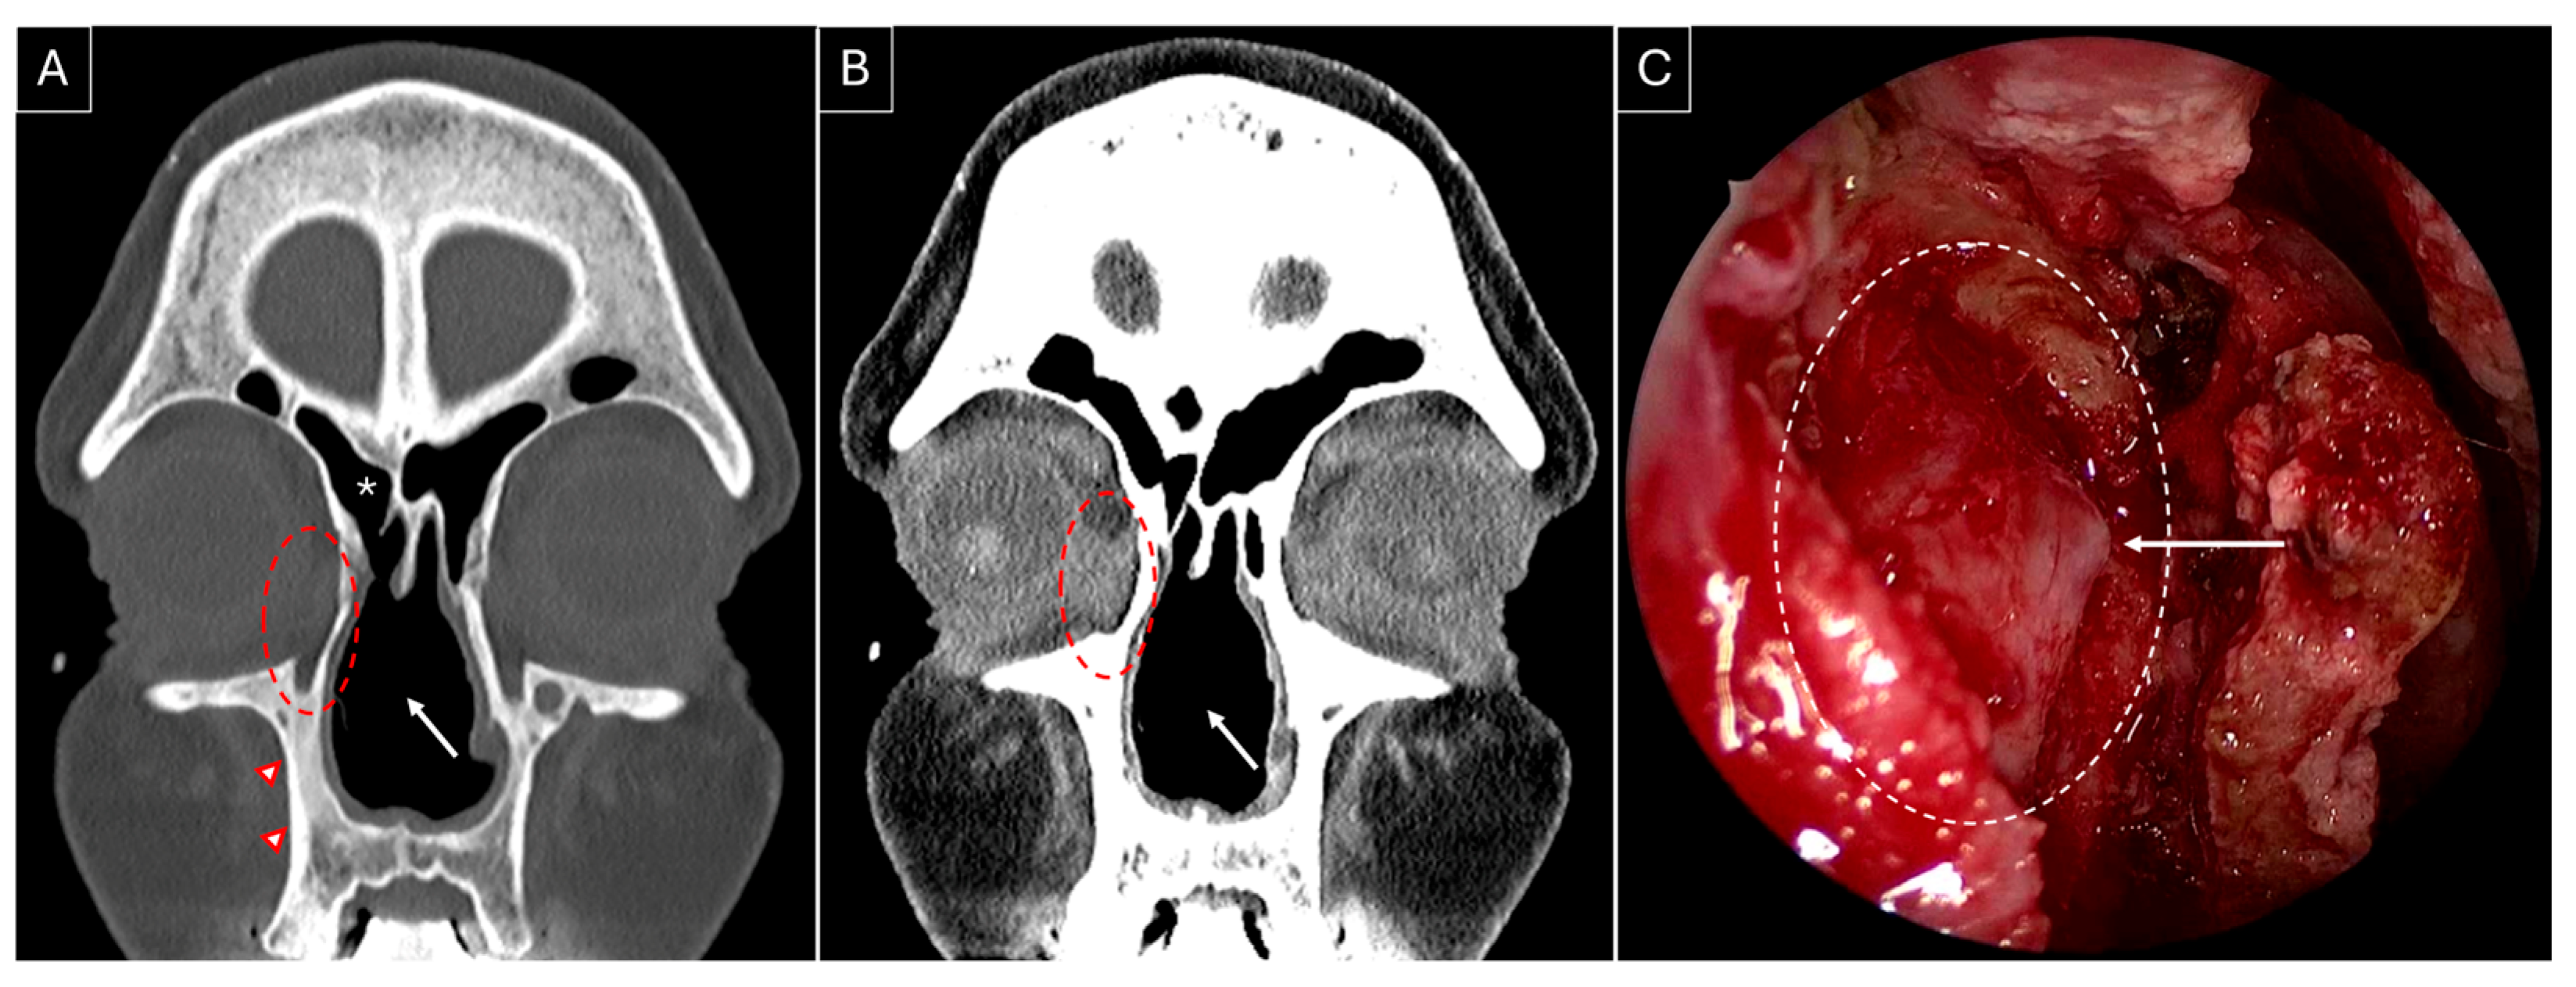

She developed complaints of right-sided epiphora in April 2023 and underwent right-sided endoscopic DCR in August 2023; Figure 3A,B highlight the sinonasal radiological findings prior to surgery. Wide marsupialization of the lacrimal sac was ensured with the placement of a Crawford stent (Figure 3C). Histopathology revealed moderate inflammation, extensive fibrosis, and squamous metaplasia. Serial debridements were performed to deal with extensive crusting at the surgical site, which settled by the seventh postoperative month, along with a complete resolution of her symptoms with low-dose methotrexate maintenance therapy.

Figure 3.

Non-contrasted sinus CT, coronal section, bone (A) and soft tissue (B) windows, showing right-sided dacryocystitis (red dotted circle). The presence of a nasal septal perforation (white arrow), osteitic bone remodelling (red arrowheads), and a previously performed right-sided hemi-modified Lothrop frontal sinusotomy can be noted (white asterisk). (C) Intraoperative endoscopic image of the right lacrimal sac medial wall (white dotted circle) after removal of the overlying lacrimal bone. The white arrow indicates tenting of the medial wall of the right lacrimal sac by the Bowman lacrimal probe.

A key observation from our review is the high success rate (100%) in endoscopic DCR over two decades (1998–2019), with no reported perioperative complications. While the sample size remains small (22 surgeries), several studies proposed methods to optimize surgical success in GPA patients, including the use of a preoperative CT for surgical planning [5,6,7,8,10], fiberoptic guidance and dye to accurately identify the lacrimal sac and distinguish the sac lumen from inflamed, thickened sac walls [8], use of silicone or Crawford tubes for lacrimal stenting to maintain postoperative patency [5,6,8,10], and high-volume postoperative saline and budesonide nasal irrigation, combined with early surgical debridement, to minimize scarring and obstruction [10]. However, none of these reports discuss patient-specific factors influencing the decision to use stenting. At our center, we routinely obtain preoperative CT scans for GPA patients undergoing endoscopic DCR, especially in cases with distorted intranasal anatomy to allow for intraoperative image guidance. It also aids in the assessment of coexisting sinus disease and the need for simultaneous sinus surgery. Our surgical protocol includes a posteriorly based mucoperiosteal flap for lacrimal bone exposure, which is then drilled to achieve complete sac exposure. A Bowman’s probe is inserted to tent the medial wall of the sac, guiding the incision (Figure 3C). Lacrimal puncta are serially dilated, followed by the use of Crawford tubes for lacrimal stenting, which are removed between 3 and 6 months postoperatively based on disease activity. Postoperative follow-up and serial endoscopic debridements are usually scheduled for the first week, sixth week, and third month. Patients are advised to perform low-pressure, high-volume saline nasal irrigations postoperatively. Given that most available data are limited to case reports and small case series (maximum sample size in reported case series = 7) [9], sharing our experience with two successful cases contributes valuable insights to the limited literature on endoscopic DCR outcomes in GPA-related epiphora.